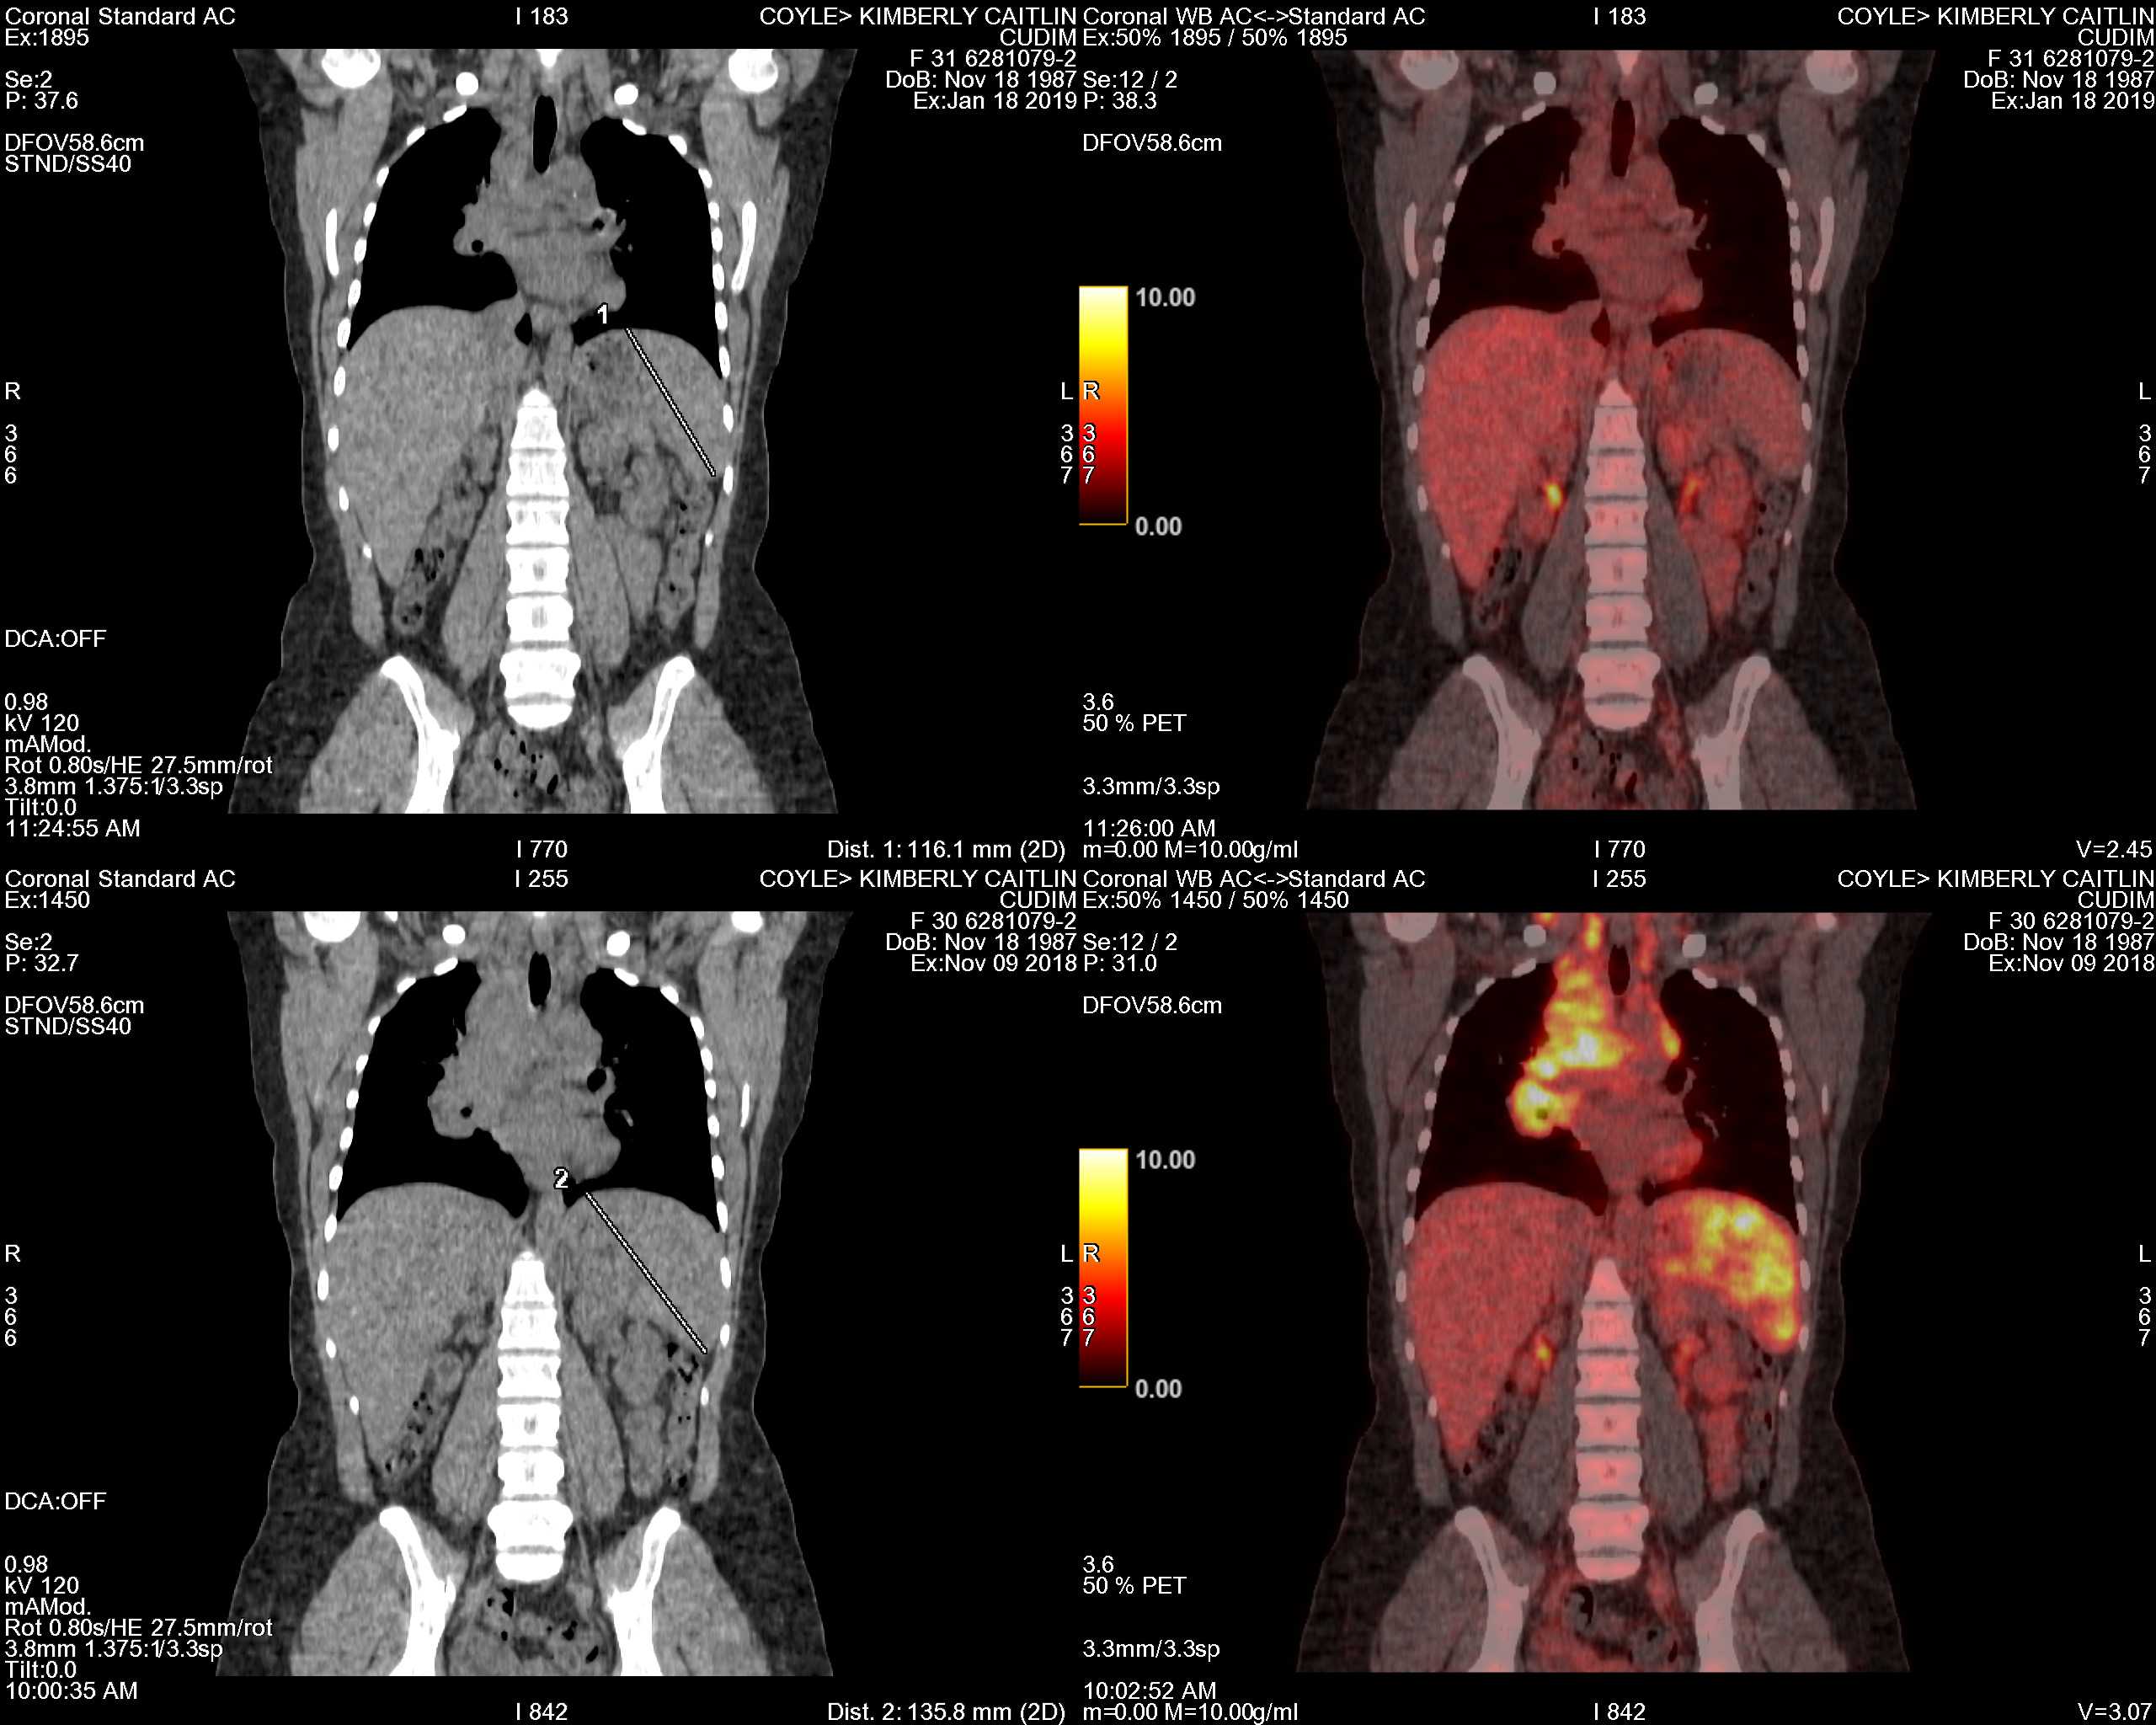

PET Scan Number Two

The Results Are In…Chemo Works

full body color

January 23, 2019